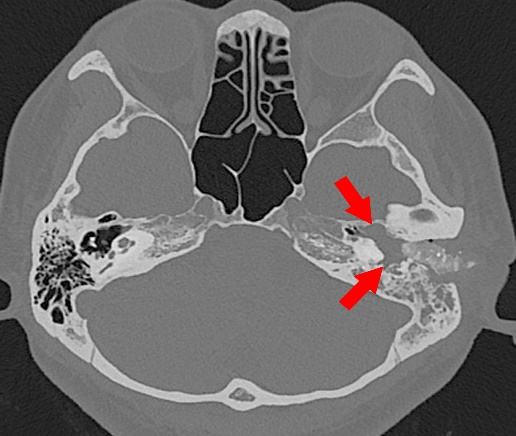

四十多岁的张女士在6月前无明显诱因出现左耳持续性“心跳声”耳鸣,听力逐渐变差,严重影响了她的日常生活。在外院诊断为中耳炎并行手术治疗,术中发现鼓室内血管瘤样肿物,为进一步寻求治疗,转投二附院,以“颈静脉球瘤(鼓室体瘤)收住耳鼻咽喉头颈外科手术治疗。该肿瘤富含血管,范围较大,充满整个中鼓室,侵犯下鼓室、后鼓室、上鼓室、鼓窦和部分乳突腔,而且系二次手术,术中出血多、手术难度大。吴宝俊教授组织团队术前讨论,制定详细的术前准备和手术方案。元旦收假后第一天,手术在吴宝俊教授的指导下由李阳副教授主刀,在麻醉科张珍妮副主任医师、手术室张曦主管护师、耳鼻喉科杨飞轮,加伟、强茵医师的全力配合下顺利开始,并全程在耳内镜下经耳道双手操作完成,耗时3小时40分,完全切除肿瘤,并同期进行听力重建,出血不到50ml。术后第一天患者耳鸣完全消失,听力提高,术后第三天,顺利出院。

鼓室体瘤,即鼓室颈静脉球副神经结瘤,临床少见。根据其来源和范围,分为FischA、B、C三型。本例患者系B2型,既往需要耳后切口行显微镜下手术,创伤较大。而传统的耳内镜手术,因单手操作难以控制肿瘤的汹涌出血。本例手术采用双手操作,有效的解决了此问题,也是吴宝俊、李阳副教授团队自2018年成功开展西北首例耳内镜下单手操作鼓室体瘤(B1型)切除术后的又一次创新,手术创伤更小、时间更短、出血量更少。近年来,耳鼻咽喉头颈外科病院在任晓勇主任的带领下,不断开展耳内镜下创新技术、挑战疑难手术,树立耳外科微创手术的品牌形象,不断带动了学科的整体发展,也为患者提供更加优质的诊疗方案。